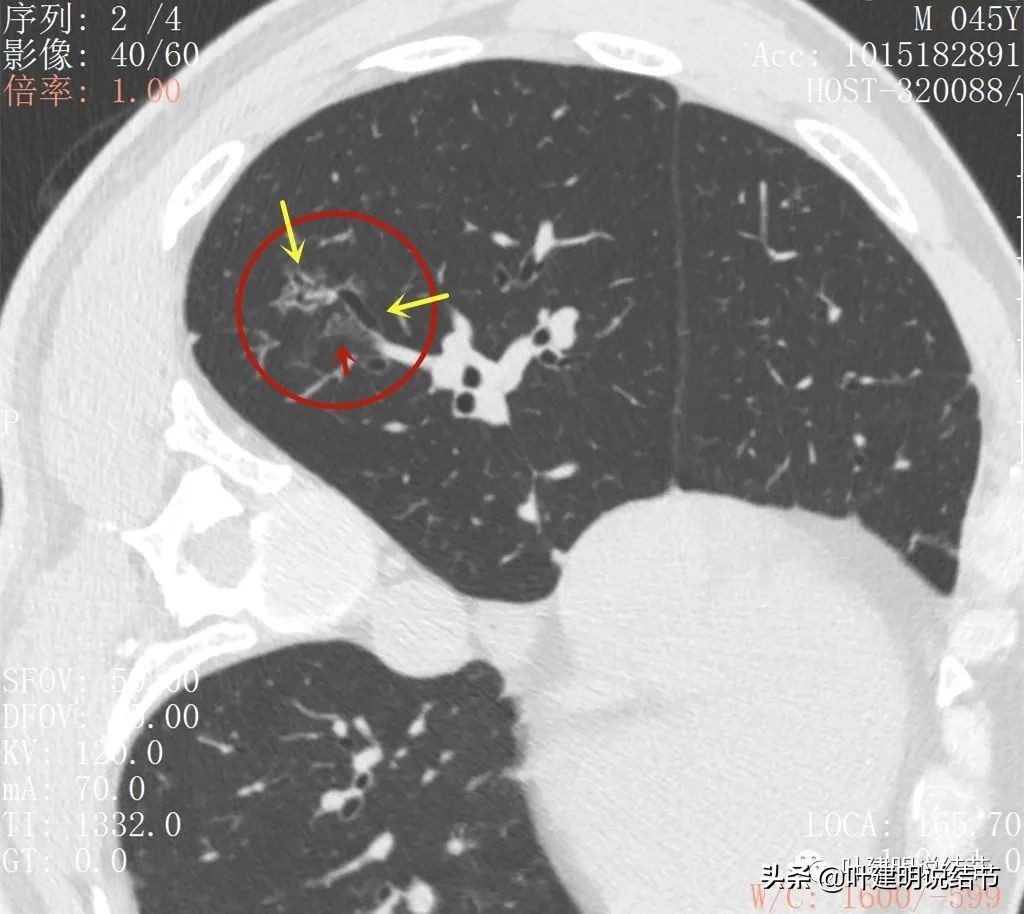

再来看薄层扫描:

病灶感觉很散在,但内部有扩张的细支气管(黄色箭头)、边缘略显不清(绿色箭头),部分有偏实性(粉色箭头)。

边缘血管异常增粗(桔色箭头),边缘显糊(绿色箭头),细支气管扩张(黄色箭头)

病灶似乎非圆形或类圆形,扩张的细支气管壁密度偏高(蓝色箭头),感觉比较僵硬(黄色箭头),病灶轮廓显模糊(黄色箭头)

扩张细支气管壁密度较高,病灶轮廓显糊